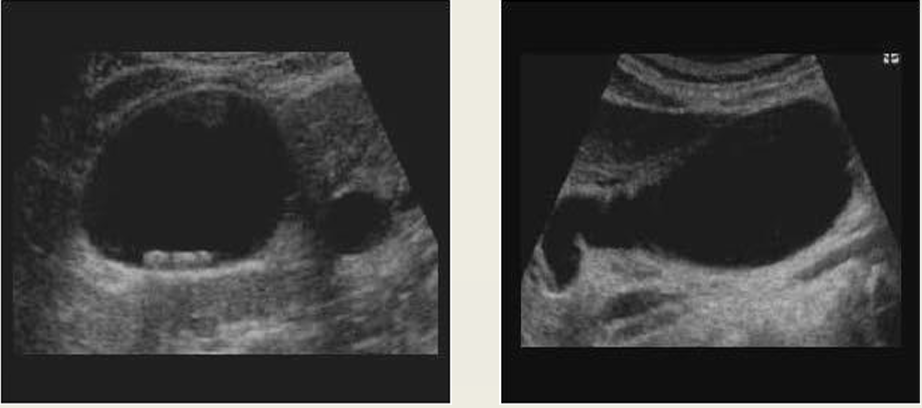

cholelithiasis

WES sign